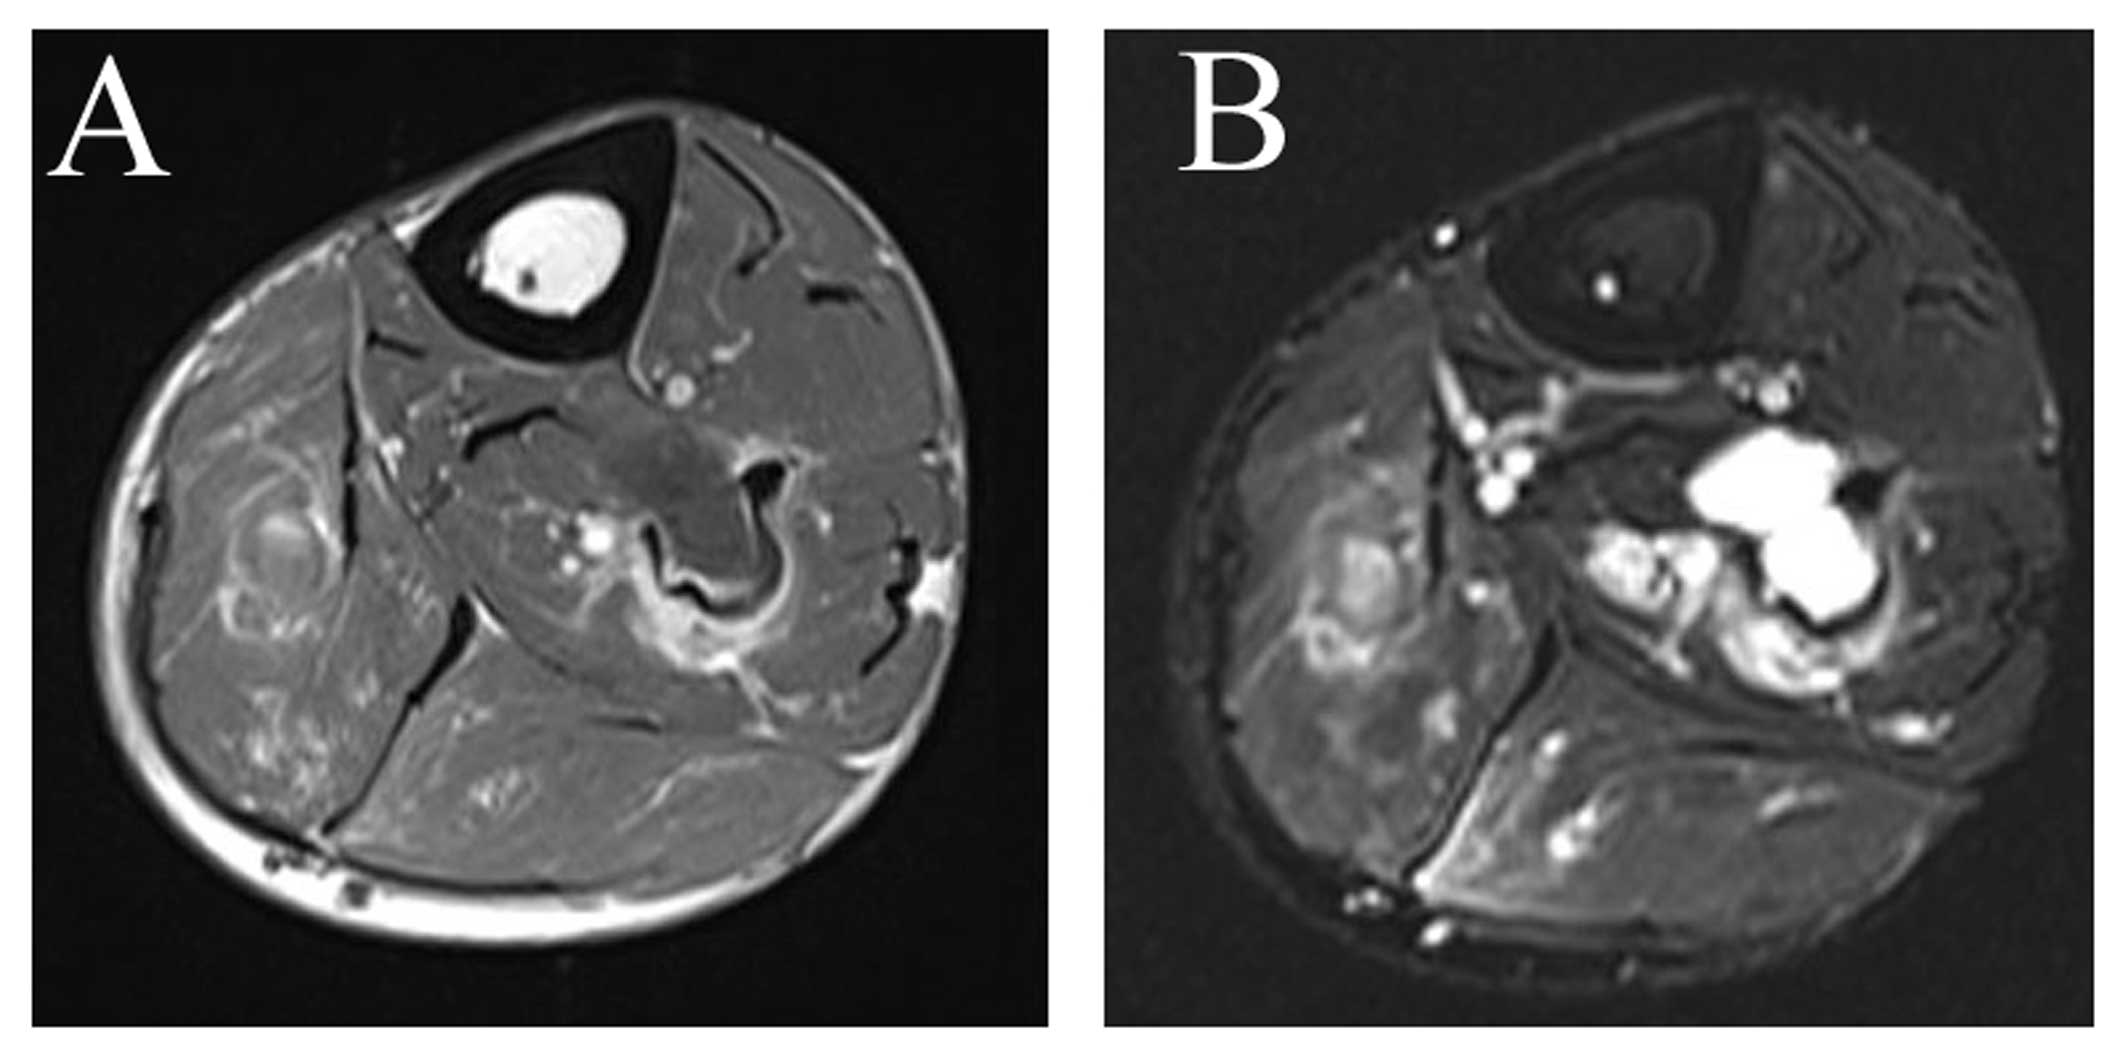

A 65-year-old male patient presented in November 2015 with left lower limb pain after spraining his left ankle 2 months prior. An X-ray film of the left lower limb revealed a wide area of destruction of the fibula. A computed tomography (CT) examination revealed a 18-cm lesion in the proximal fibula, with breakthrough of the cortical of the fibula in places (Fig. 1). On magnetic resonance imaging (MRI) examination, the lesion presented as a well-defined fluid collection with low intensity on T1-weighted images and very high intensity on T2-weighted images (Fig. 2). On certain slices, a soft tissue mass growing out of the fibula was observed (Fig. 3). The patient was a non-smoker and the chest CT excluded lung cancer. The initial suspected diagnosis was a fibular invasive tumor, and metastasis could not be excluded. An open biopsy was scheduled and a transparent, jelly-like material oozed out of the cavity when the bone cortex was drilled. In addition, white lime-like material was observed on the cavity wall. The frozen section biopsy revealed a wall consisting of a fibrous capsule and bone tissue, and the lesion was considered to be benign (Fig. 4). As the lesion was extensive, wide resection was performed. The histological examination later confirmed that the lesion was an intraosseous ganglion (Fig. 5). At 3 months after surgery, the patient was able to walk normally and had no complaints of pain. The patient attended the clinic every 3 months. At the 3-month follow-up, the patient was able to walk normally and had no complains of pain. After 6 months, an X-ray of the fibula was performed and the patient remained recurrence-free.

Figure 2.

On magnetic resonance imaging, the lesion exhibited (A) low intensity on T1-weighted images and (B) very high intensity on T2-weighted images.